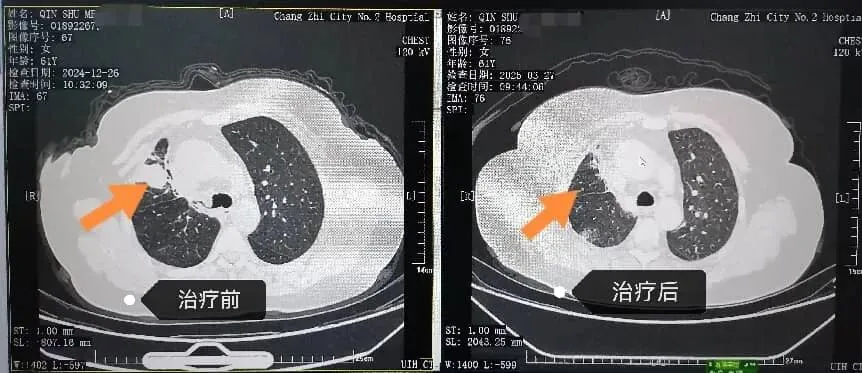

一位61岁女性,七年前腺癌术后复发,在一代靶向药显效多年后出现耐药。我们通过动态基因监测,及时捕捉到耐药信号,果断更换三代靶向药物。一月后,复查显示肿块显著缩小。体现了长治二院呼吸与危重症医学科“全程监测、精准序贯”的靶向治疗理念,将晚期肺癌转化为需要长期管理的慢性病。